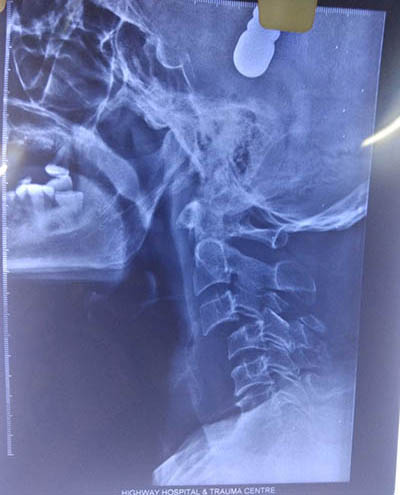

He has treated numerous complex spine ailments like metastatic tumors, osteoporotic fractures (vertebroplasty), degenerative diseases and listhesis etc.